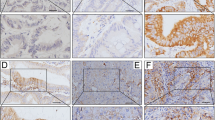

Tumor PD-L1 expression and CD8+ intra-tumoral infiltrating lymphocytes were analyzed by immunohistochemistry (IHC) and examined in tumor tissues and adjacent normal mucosae. PD-L1 was detectable in epithelial cells from normal colonic mucosae and cancer cells (Fig. 1). The clinicopathologic characteristics of patients and the correlation with PD-L1 expression in pre-neoCRT biopsies and post-neoCRT surgical tissues are presented in Table 1.